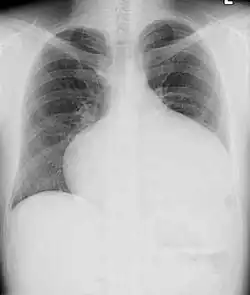

Adults with an uncorrected ASD present with symptoms of dyspnea on exertion (shortness of breath with minimal exercise), congestive heart failure, or cerebrovascular accident (stroke). They may be noted on routine testing to have an abnormal chest X-ray or an abnormal ECG and may have atrial fibrillation. If the ASD causes a left-to-right shunt, the pulmonary vasculature in both lungs may appear dilated on chest X-ray, due to the increase in pulmonary blood flow.[36]

In transthoracic echocardiography, an atrial septal defect may be seen on color flow imaging as a jet of blood from the left atrium to the right atrium.

If agitated saline is injected into a peripheral vein during echocardiography, small air bubbles can be seen on echocardiographic imaging. Bubbles traveling across an ASD may be seen either at rest or during a cough. (Bubbles only flow from right atrium to left atrium if the right atrial pressure is greater than left atrial). Because better visualization of the atria is achieved with transesophageal echocardiography, this test may be performed in individuals with a suspected ASD which is not visualized on transthoracic imaging. Newer techniques to visualize these defects involve intracardiac imaging with special catheters typically placed in the venous system and advanced to the level of the heart. This type of imaging is becoming more common and involves only mild sedation for the patient typically.

If the individual has adequate echocardiographic windows, use of the echocardiogram to measure the cardiac output of the left ventricle and the right ventricle independently is possible. In this way, the shunt fraction can be estimated using echocardiography.